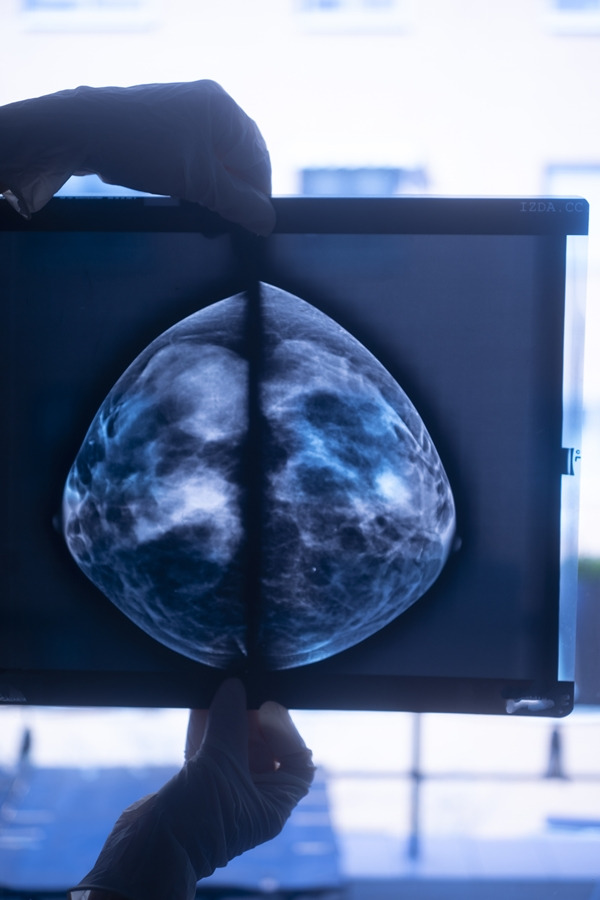

유방암(breast cancer)은여성암 중 발병률이 2위에 해당합니다.

유방암 초기에는 대부분 아무런 증상이 없으므로 여성이라면 더 주의를 기울여야 하는 암종입니다.

특히 유방암 발병률이 상대적으로 높을 수 있는 고위험군 여성이라면 더더욱 주의가 필요합니다. 유방암 원인은 무엇인지, 그리고 어떤 분들이 유방암 고위험군에 속하는지 살펴보겠습니다.

유방암 고위험군이라면 건강한 생활습관을 유지하기 위해 노력해야 합니다. 그러나 이보다 더 중요한 것은 정기적인 검진과 추적 관찰입니다. 유방암은 조기에 발견해 치료하면 생존율이 매우 높으므로, 30~40대 이상 여성이라면 임상 진찰과 정기적인 검사를 꼭 받으시길 권합니다.